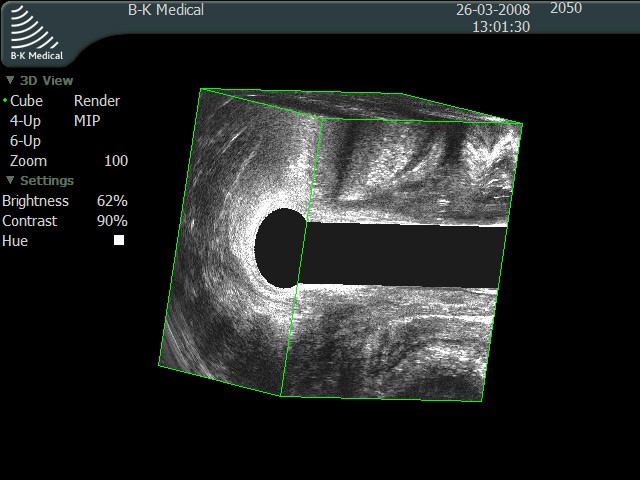

При ректальном обследовании стенка имеет пять слоев, причем второй и четвертый имеют гипо-эхогенные свойства, а остальные – гиперэхогенны. Лимфоузлы визуализируются только параректальные, и их толщина не более пяти миллиметров. Контуры органа ровные, без изменений.

УЗИ прямой кишки.

УЗИ ректальным датчиком (ЭРУЗИ) позволяет точно определить наличие патологического процесса, его локализацию, размеры, характер и количество содержимого в случае наличия полости, глубину расположения патологического очага, инфильтрацию тканей, наличие и протяженность свищевых ходов, их отношение к мышечному аппарату